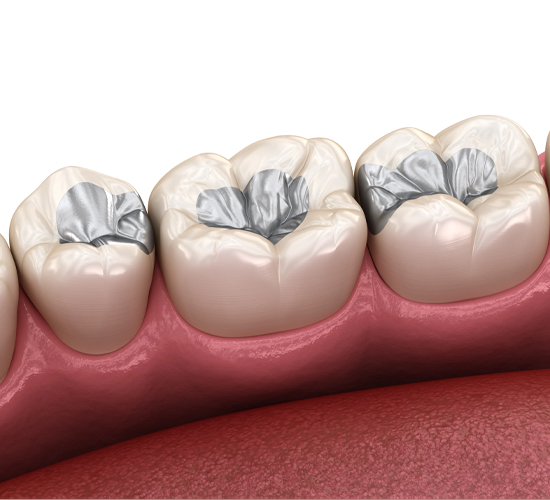

About 92 percent of the population will have at least one cavity in their lifetime.